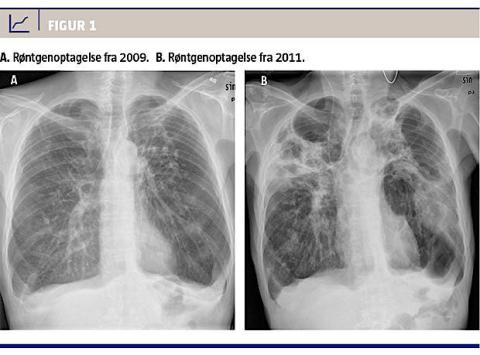

En 59-årig mand blev indlagt med pneumoni og sepsispræg. Han havde svær KOL samt blærepapillomer og fulgtes i et kontrolforløb efter BCG-installationer mod disse lidelser. Patienten var i dårlig almentilstand og havde haft et utilsigtet vægttab på 12-14 kg over 2-3 måneder op til indlæggelsen Herudover havde han et alkoholoverforbrug. Da pneumonien var behandlingsresistent, rejstes der mistanke om tb (Figur 1). Patienten var ti år tidligere blevet behandlet for pulmonal tb. Pga. mistanke om recidiv af tb blev der sendt to ekspektorater til undersøgelse for mykobakterier. På National Afdeling for TB og Mykobakterier påviste man syre-alkohol-faste stave ved auramin-rhodamin-farvning og PCR var positiv for